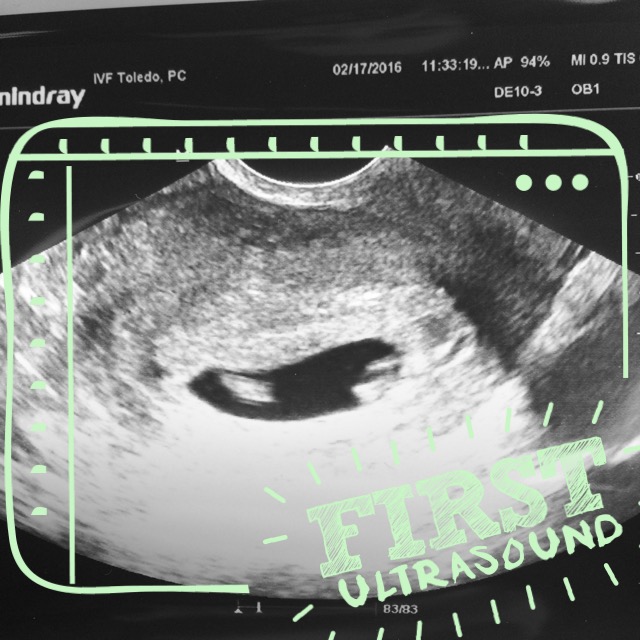

We went in for our first ultrasound when I was 6 weeks and 4 days along. Nick took a half day off from work so that he could come with me. I picked him up from our house and we rode together to the doctor’s office. On the way, we heard a commercial about a woman hearing two heartbeats at her ultrasound and she found out she was having twins. Nick looked at me and said something along the lines of “that could be us, maybe it’s a sign”. I laughed it off and said, yea right! We only transferred one embryo, it was a miracle in itself that that had stuck!

My doctor was out of the office that week so I was seeing one of the ultrasound techs. As soon as she stuck in that magic want I immediately saw two little white blobs. But then she started moving it around and they were gone just as fast. The first thing she said was “there it is”, and I finally let my breath out (I think I had been holding it since the blood draw). She took its measurements, and showed us the little flicker of the heartbeat. I was grinning from ear to ear. They warned me that we might not be able to hear the heartbeat this early, but we could try. I held my breath again and all of a sudden heard the most beautiful sound, the thump-thump-thump of my baby’s heart. Queue the tears.

After that, I’m not sure what came over me, but that is when I blurted out the “are you sure there aren’t two in there?” She said, “Well hold on let me check, I am going to do a scan of the uterus.” I watched the screen change and then she stopped on another blob and said “Yep, there’s another.” Well HOLY CRAP. TWINS!!! Disbelief, shock, joy, fear, excitement – I felt all of these emotions in that single moment. We were able to hear the heartbeat of baby 2 as well!